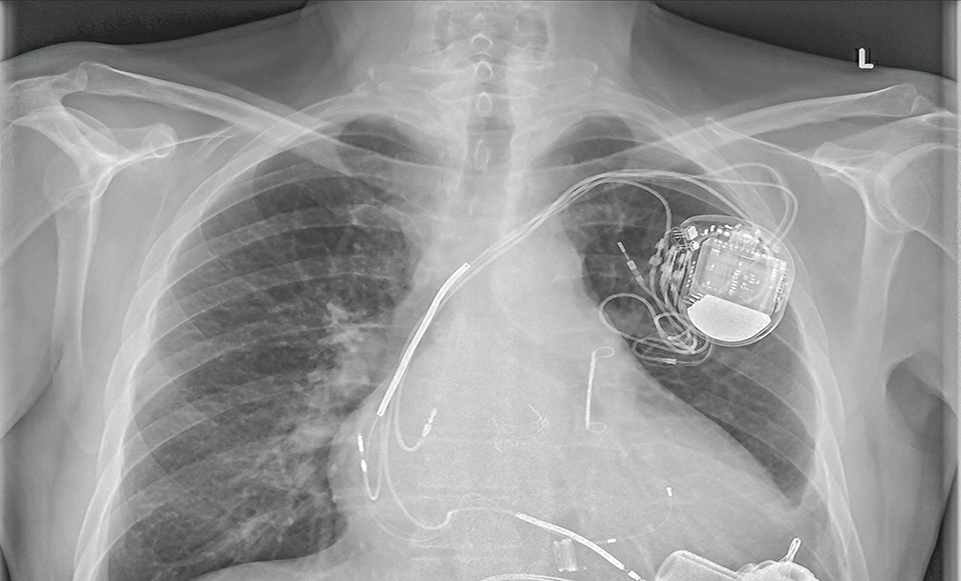

永久性起搏器植入术

永久性心脏起搏器植入术是目前治疗严重缓慢性心律失常的重要手段。随着起搏器技术的不断进步,其应用范围已从单纯治疗缓慢性心律失常,扩展到快速性心律失常、晚期心力衰竭及心肌病等疾病领域。手术通过将起搏器植入皮下,发放特定电脉冲刺激心脏,模拟正常心脏的冲动形成和传导,促使心脏规律性收缩,从而改善心脏功能,降低病死率,显著提高患者的生活质量。术后注意要点:(一)日常护理肢体活动术后一周可逐步进行肢体功能锻炼